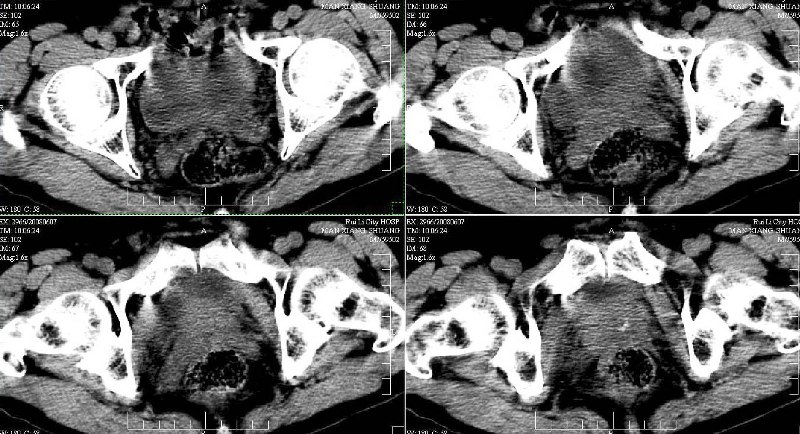

ct(椎间盘扫描):椎间盘炎,建议dr。

dr:l4骨质破坏,转移可能。

胸部摄片未见异常。临床医生体检发现上腹部饱满。

ct:肝癌腰椎转移。临床医生:肝脏、骨转移,肿瘤来自?前列腺?!